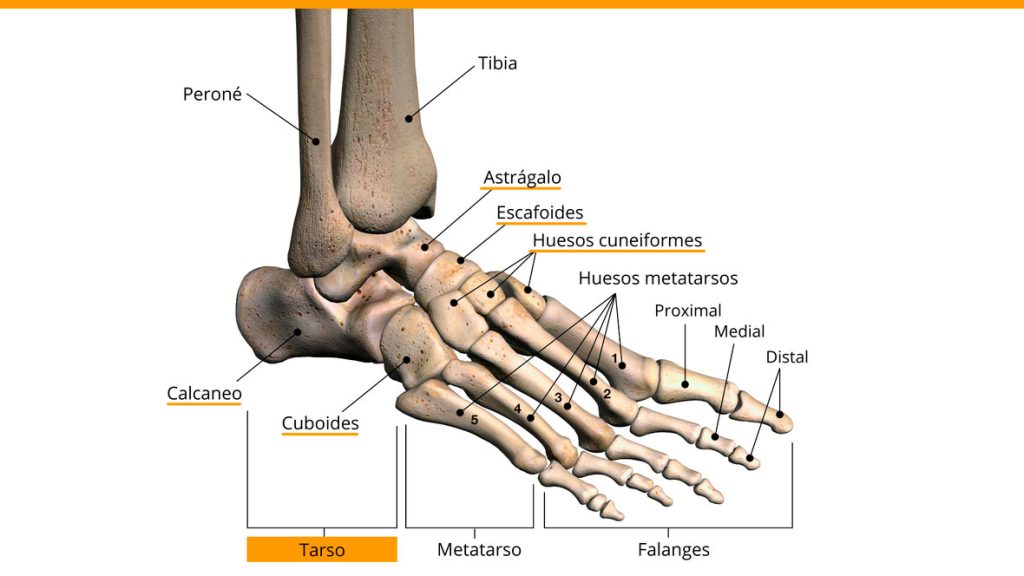

El pie está compuesto por 26 huesos en total. Estos huesos se dividen en 3 grupos, que son el Tarso, el Metatarso y las Falanges. Dentro del grupo del Tarso, encontramos 7 Huesos (Astrágalo, Calcáneo, Cuboides, Navicular y los Primero, Segundo y Tercer Cuneiformes), estos son los que están “debajo de la pierna”. Después encontramos el Metatarso, que está formado por 5 huesos largos que unen el Tarso con las Falanges, estos son los que están en la zona del empeine. Y finalmente encontramos las Falanges, que son los huesos de los dedos de los pies.